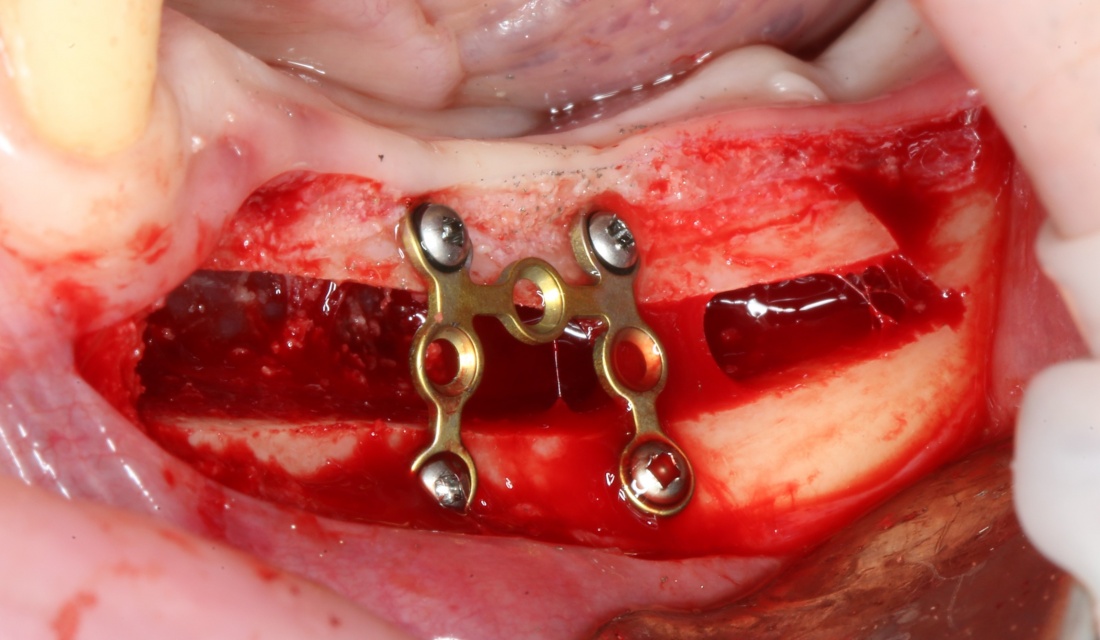

При горизонтальной остеотомии, на мой взгляд, удобнее использовать минипластины. Как я уже отмечал выше, в практике мы используем X- и H-образные минипластины под винты размером 0.9х4мм. Количество металла в разных условиях может быть разным — всё зависит от того, на каком этапе достигается полная неподвижность перемещенного костного фрагмента.

В какой момент это делать? Наверное, если Вы используете графт в виде твердого блока, то, мне кажется. разумнее сначала уложить графт, затем проводить фиксацию перемещенного костного фрагмента винтами или минипластинами: